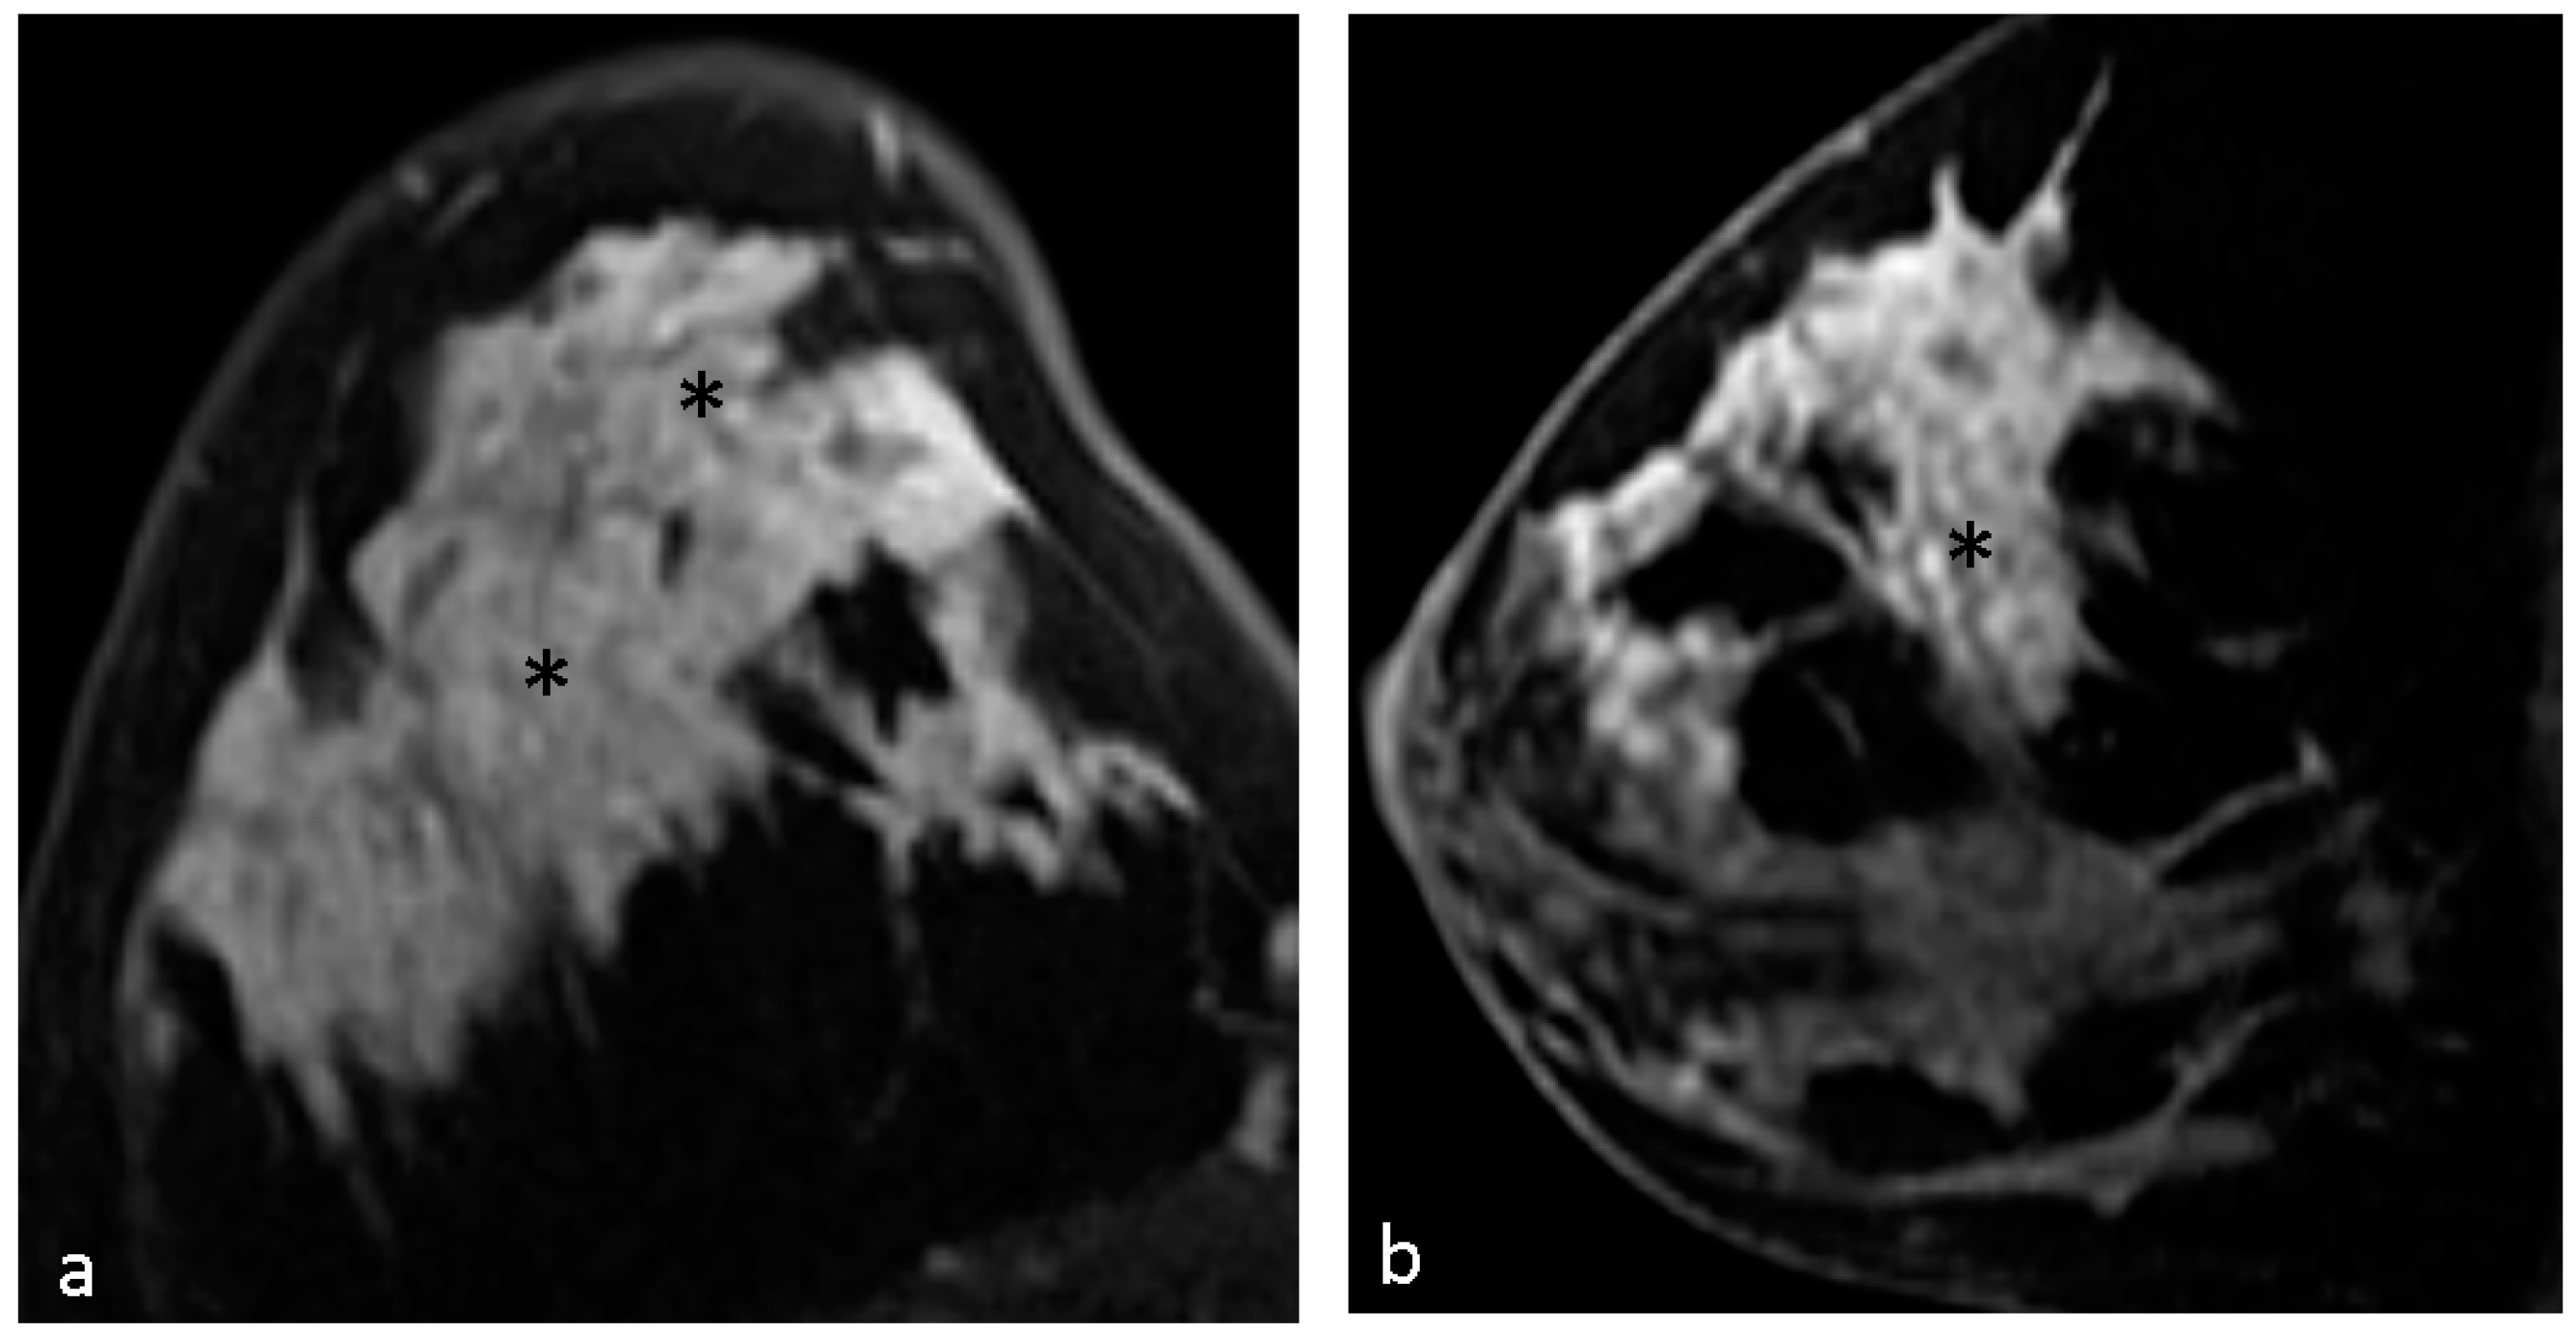

| Clustered ring enhancement | 31 (53.4%) |